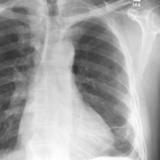

Rounded atelectasis case 2